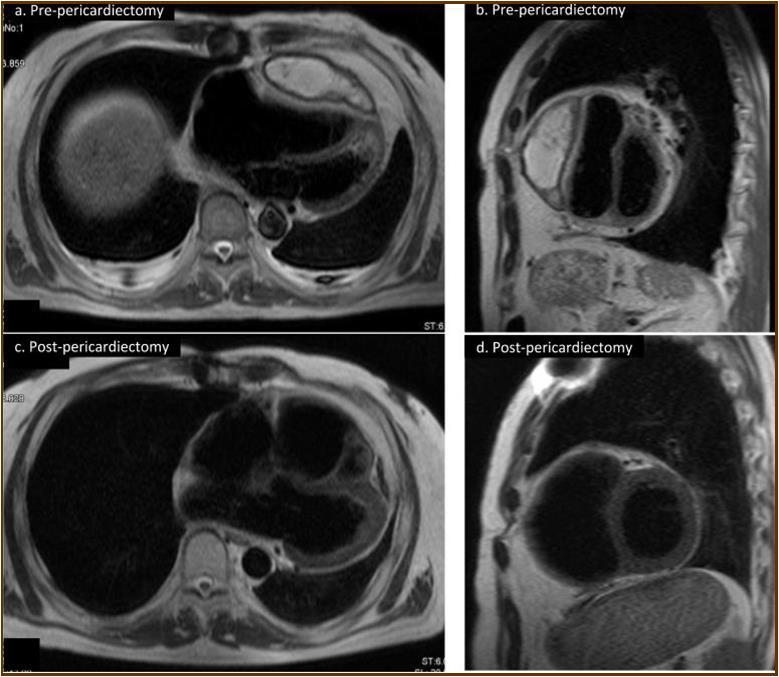

Figure 2.Magnetic resonance imaging findings. A thick cystic-like capsule which was tightly adhered to the right ventricle was seen (a. transverse view; b. sagittal view). A cystic-like capsule was removed after pericardiectomy (c. transverse view; d. sagittal view).

At the age of 52 years, the patient was admitted to our institution for both evaluation of heart failure and regular right heart catheterization including EMB. With respect to allograft rejection, ACR was again detected on regular EMB, and the immunosuppressive regimens were strengthened. Further echocardiographic investigations were conducted to explore the implications of findings indicative of constrictive physiology with thickened pericardium. Respiratory variation in both mitral and tricuspid inflow velocities was seen, but these findings did not meet the complete criteria for CP diagnosis (Figure 1c-e). Magnetic resonance imaging of the heart revealed seroma and a thick cystic-like capsule tightly adhered to the right ventricle (Figure 2a, b). Right heart catheterization revealed elevation of right atrial pressure with severely reduced cardiac index (Figure 3a). The classic dip-and-plateau pattern of right ventricular diastolic pressure and equalization of right atrial pressure and right ventricular diastolic pressure were also observed (Figure 3b). Based on these results, effusive CP or cardiac tamponade-like hemodynamics were strongly suspected, although the etiology remained unknown. Therefore, at 3 years post-HTx, the patient initially underwent removal of the seroma through exploratory lateral thoracotomy to elucidate the etiology of the disease. Yellowish fluid was found and the fluid was completely aspirated. Immunosuppressive regimens including everolimus, which may interfere wound healing, were temporarily converted to standard three-drug regimens. Removal of the seroma via lateral thoracotomy did not lead to improvement in symptoms or hemodynamics. Pathological analysis revealed fibrin and seroma, but no malignant cells or infection. Since the initial procedure did not have any effect on the patient’s symptom, pericardiectomy through median sternotomy was performed at two months after the initial procedure. Intraoperative findings indicated a thickened pericardium and effusion in front of the right ventricle. At first, after sternotomy and adhesiotomy, the tissue in front of the right ventricle, which appeared to be thickened parietal pericardium, was completely resected and the effusion fluid was removed. However, high central venous pressure (20 mmHg) persisted, resulting in a displacement of the left ventricle by the right ventricle. Therefore, additional tissue from the front of the right ventricle was excised, corresponding to diffusely thickened visceral pericardium and epicardium. After the procedure, central venous pressure decreased from 20 to 10 mmHg, and displacement of left ventricle resolved. Pathological analysis of the resected tissues demonstrated chronic fibrosis and chronic inflammation with plasma cells, but no infectious etiology was identified (Figure 4 a, b). After the pericardiectomy, hemodynamics (Figure 3a, c) and symptoms improved, and the patient is currently experiencing a favorable clinical course without complications.